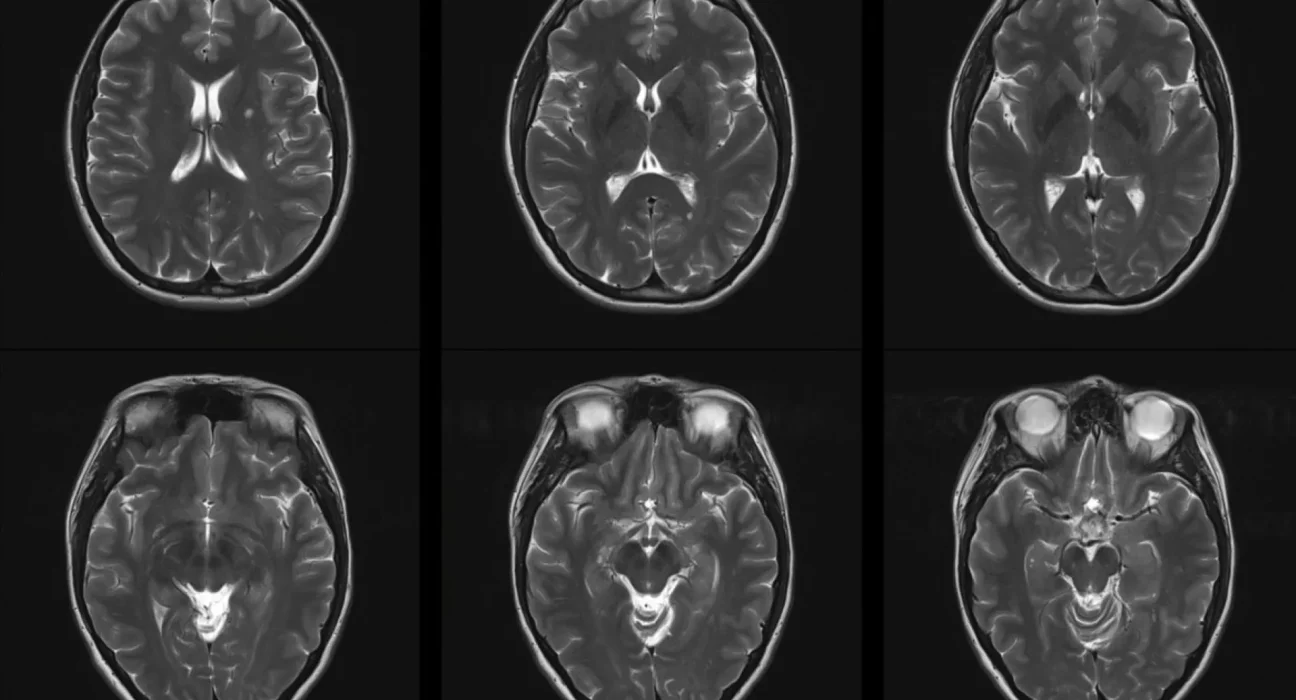

La pollution de l’air est souvent désignée comme un « tueur invisible », et les dernières recherches renforcent cette image. Une étude récente a mis en évidence un lien préoccupant entre l’exposition à l’air pollué et le risque de développer la sclérose en plaques (SEP). Elle souligne également que la pollution peut aggravé la condition chez les personnes déjà atteintes.

Les résultats révèlent qu’une exposition prolongée aux particules fines (PM2.5) augmente le risque de SEP de 21 %. Pour des particules légèrement plus grosses, d’un diamètre inférieur à 10 micromètres, ce risque grimpe à 20 %. Cependant, pour d’autres polluants tels que le monoxyde de carbone ou le dioxyde de soufre, aucune association significative n’a été trouvée pour le développement de la maladie. En revanche, les personnes déjà atteintes de SEP voient leur santé se détériorer lorsqu’elles sont exposées à ces polluants de manière temporaire, ce qui peut entraîner des lésions et une augmentation des risques de rechute.

Le message des experts en santé publique est clair : un air plus pur est crucial. Cette étude offre des preuves solides soutenant l’idée que la pollution de l’air peut non seulement déclencher la sclérose en plaques, mais également augmenter son intensité et sa sévérité, notamment par le biais des rechutes et de la progression des incapacités.